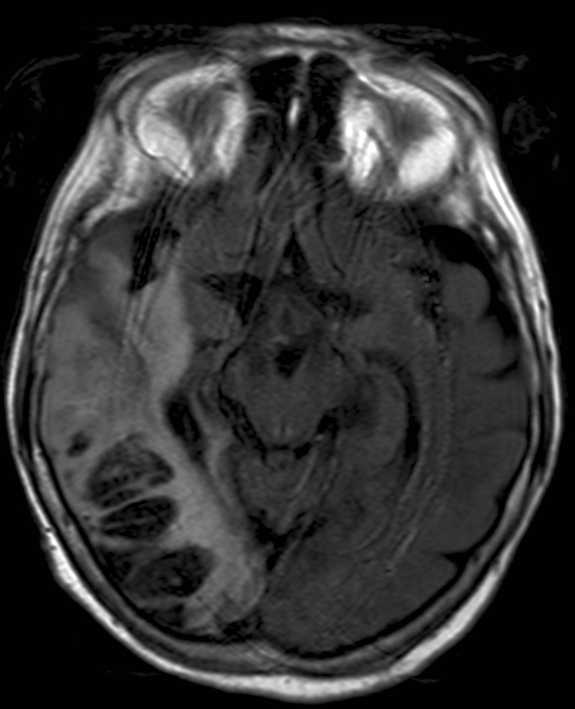

• Sinus thrombosis can occur in any of the intracranial sinuses. However, only cavernous sinus thrombosis constitutes a medical emergency. Facial, orbital, intracranial infections may be associated with sinus thrombosis. If available MRI is the method of choice to diagnose a suspected sinus thrombosis, or similar to other vascular diseases a contrast enhanced CT should be performed (MR and CT venography). Otogenic processes (e.g. mastoiditis) are frequently complicated with thrombosis of the sigmoid sinus.

13. Old woman with headache and altered mental status. Unenhanced and contrast enhanced CT scans show a hypodense lesion with gyral hyperdensity The location does not correspond to any arterial territories. On MRI it proved to be a bleeding. Lack of enhancement in the right transverse sinus indicates thrombosis.